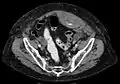

Rectus sheath hematoma seen on axial CT – with active bleeding under Marcoumar- Rectus sheath hematoma as seen on ultrasound[2]